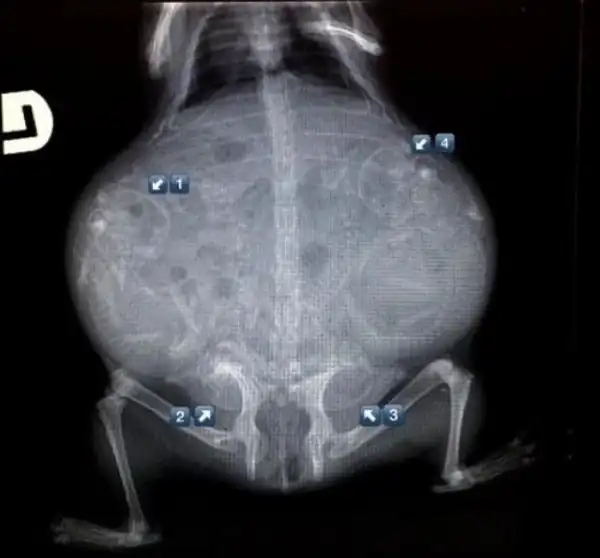

Беременная морская свинка